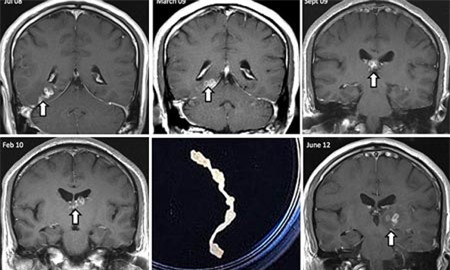

Một con giun sở hữu bộ gen dài bất thường đã sống trong đầu, gần bộ não của một người đàn ông Anh suốt 4 năm, khiến khổ chủ điêu đứng cả thời gian dài, theo một nghiên cứu mới.